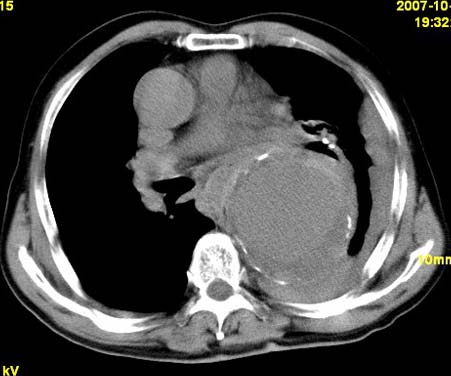

标题: CT10190:男,70,胸部疼痛数年,加重一天。典型病例。 [打印本页]

标题: CT10190:男,70,胸部疼痛数年,加重一天。典型病例。

典型降主动脉瘤伴血栓形成.瘤体下部局部边缘不清,结合病史,不除外局部撕裂外渗可能.另左侧胸水,肺部压迫不张改变.建议增强进一步检查.

典型降主动脉瘤伴血栓形成。支持:降主动脉瘤!

考虑胸主动脉瘤并血栓形成,胸腔积液

1.降主动脉瘤伴血栓形成.2.左侧胸腔积液,考虑为主动脉瘤破裂所致。

降主动脉明显增粗,边缘模糊,周围低密度影,双侧胸膜腔少量积液,结合临床考虑胸主动脉瘤破裂并双侧胸腔积液。